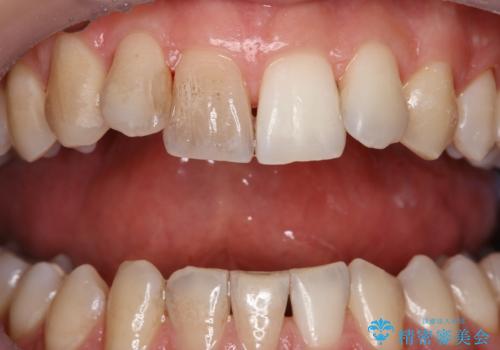

- 歯の色が気になり、ホワイトニングを考えているとのことで来院されました。

ホワイトニングは、歯の表面の汚れや着色を全て除去してからでないと効果が出にくいため、まずはクリーニングのご案内をしました。

エアフロー60分コースを行いました。

着色の除去後に、ご自身の本来の歯の色をご確認していただいたところ、この状態で満足とのことでした。